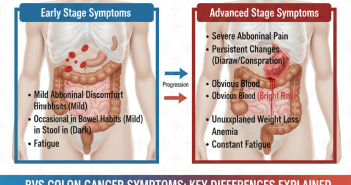

Introduction Colon cancer screening tests are designed to find cancer early or prevent it by…